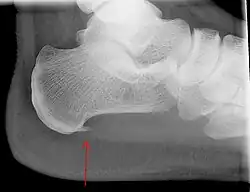

An incidental finding associated with this condition is a heel spur, a small bony calcification on the calcaneus (heel bone), which can be found in up to 50% of those with plantar fasciitis.[6] In such cases, it is the underlying plantar fasciitis that produces the heel pain, and not the spur itself.[13] The condition is responsible for the creation of the spur, though the clinical significance of heel spurs in plantar fasciitis remains unclear.[12]

Medical imaging is not routinely needed. It is expensive and does not typically change how plantar fasciitis is managed.[15] When the diagnosis is not clinically apparent, lateral view X-rays of the ankle are the recommended imaging modality to assess for other causes of heel pain, such as stress fractures or bone spur development.[7]